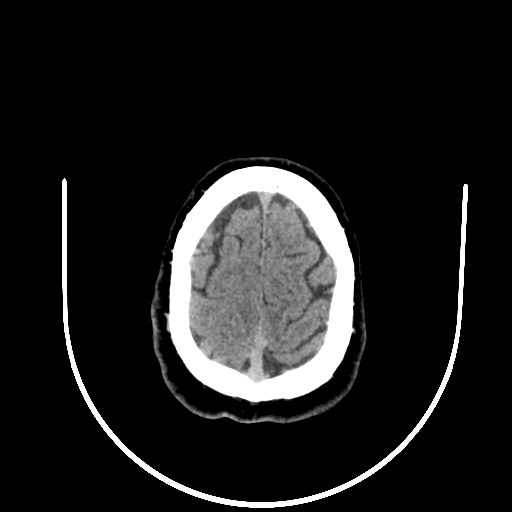

39 years old man with chronic alcoholic since 17 years.

& cough with cold & dark colour stool.

Now feeling weakness & dimness of vision.

O/E images: